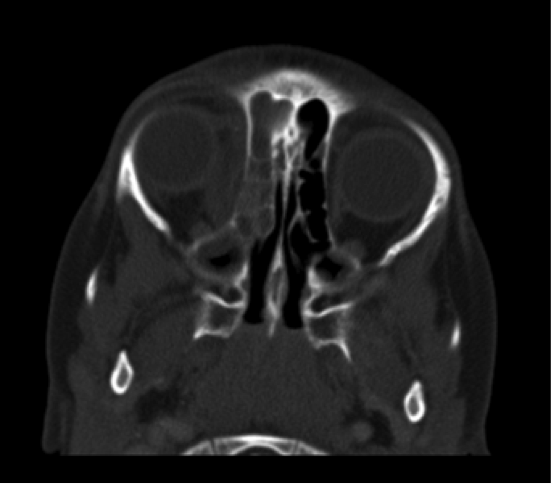

En nuestro caso, al sospechar una celulitis orbitaria, pedimos una TC y una prueba para ver la presión intracraneal (PIC) a Oftalmología.

Aquí se ven unos cortes del TC: